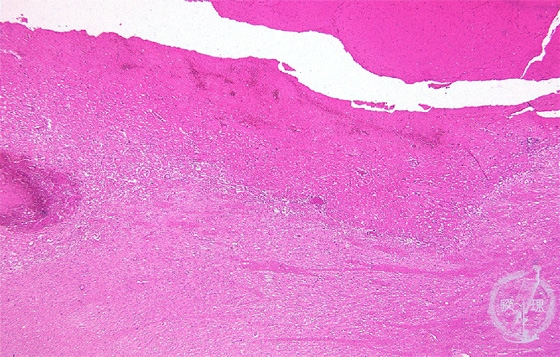

Microscopic findings (H.E. low magnification): Brain parenchyma was extensively distorted by hemorrhage and hematoma, and demonstrated liquefactive necrosis adjacent from edema (above the line). Organization started at the periphery of hemotoma (between the line and the dotted line).